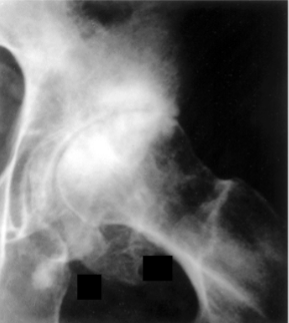

Osteoarthritis

Joint space is narrowed, but fusion (Ankylosis) does not occur

Subchondral bone sclerosis (Osteosclerosis)

Peripheral Osteophytes

Faint scattered radiolucent Subchondral Bone Cysts

Subchondral Bone Cysts